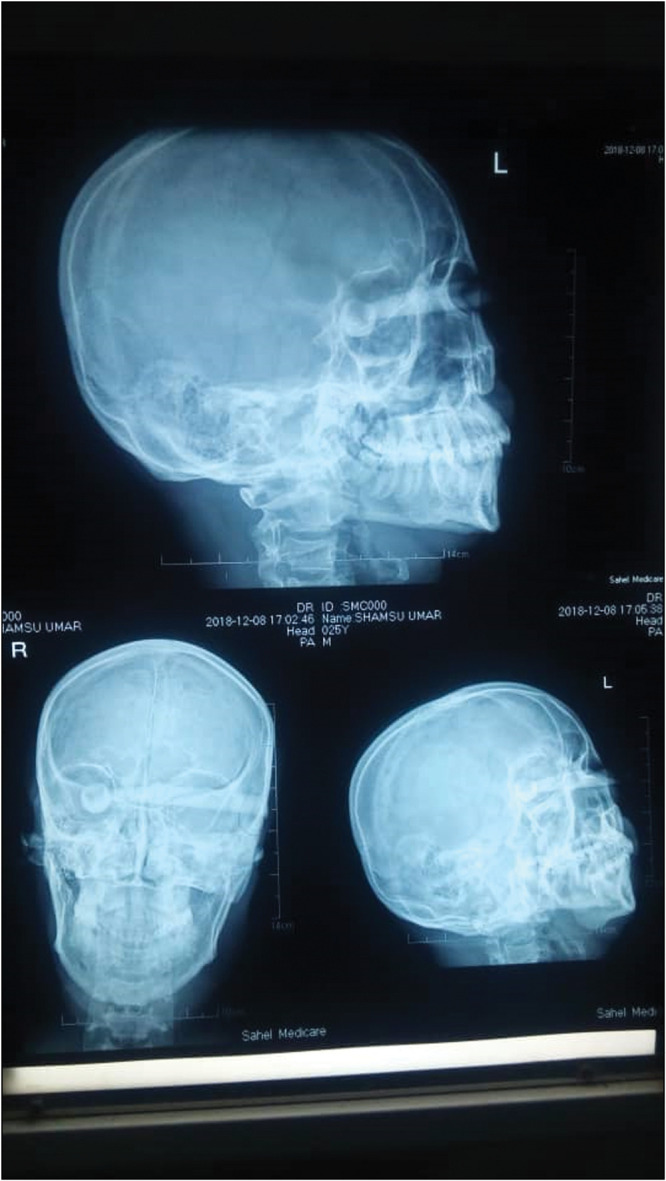

Case report: Intra-orbital FBs are rare, with few cases reported in the literature. This is because the orbit protects the globe from external forces, and the orbit is a closed cavity with one opening. This report details the case of a 28-year-old man who presented to the emergency unit with an 11-hour history of an intra-orbital FB. The patient was lying on a bench when a stationary motorcycle fell on him. He noticed that he was unable to open both eyes and was rushed to a peripheral hospital, then subsequently referred to this tertiary center. On examination, he was ill-looking and anxious but not febrile or pale. Systemic examination did not reveal any abnormality. Unaided visual acuity in the right eye (OD) was nil perception of light, while left eye visual acuity (OS) was counting fingers. The right eyelid was ptotic due to edema. He underwent basic laboratory investigations that were all normal. A plain X-ray revealed a radio-opaque FB penetrating the left orbit, fracturing the medial walls into the right orbit, with the round end positioned behind the right globe. The FB was identified as a broken part of a brake/clutch lever from the motorcycle. A computerized tomography scan showed a metallic object in both orbits, accompanied by pneumocephalus, and suggested transection of the right optic nerve. The patient was prepared for FB removal and repair of the lid penetration under general anesthesia, following review by the ENT surgeon and neurosurgeon. The brake lever was successfully removed, and the patient was administered antibiotics. Post-operatively, visual acuity in the right eye remained at nil perception of light, while that in the left eye improved to 6/9 upon discharge.